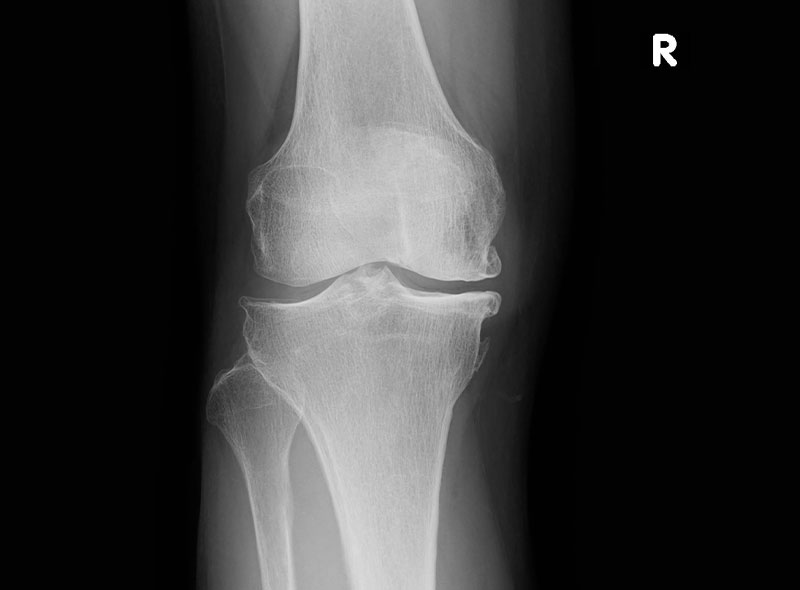

デジタルX線画像診断装置

画像の拡大縮小やコントラスト調整が可能のため診断精度が向上し、わかりやすい説明も可能です。

当院では最新のデジタルX線画像診断装置を用いて、正確な診断と被ばく量の軽減を心がけています。

レントゲン検査画像

膝(変形性膝関節症)